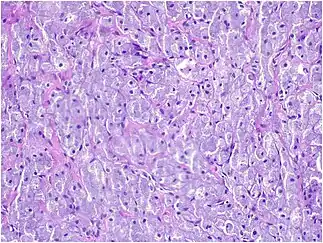

Histopathological Characteristics

Histopathologically, congenital epulis is usually characterized by the presence of big, rounded cells that fill the mucosa's lamina propria and have round to oval nuclei and an abundance of eosinophilic cytoplasm.[10] A thin layer of connective tissue separated the surface layer of cells from the growing new cells. Numerous histological traits, such as a fibrous and granulomatous appearance, have been reported in recent research.[10]

Microscopically, congenital epulis is composed of:

- Sheets of proliferating polygonal to round cells with overlying thin squamous, eosinophilic, granular cytoplasm[12][13]

- Centrally located, round nuclei [7]

These histopathological features are essential in distinguishing congenital epulis from other gingival and soft tissue neoplasms.